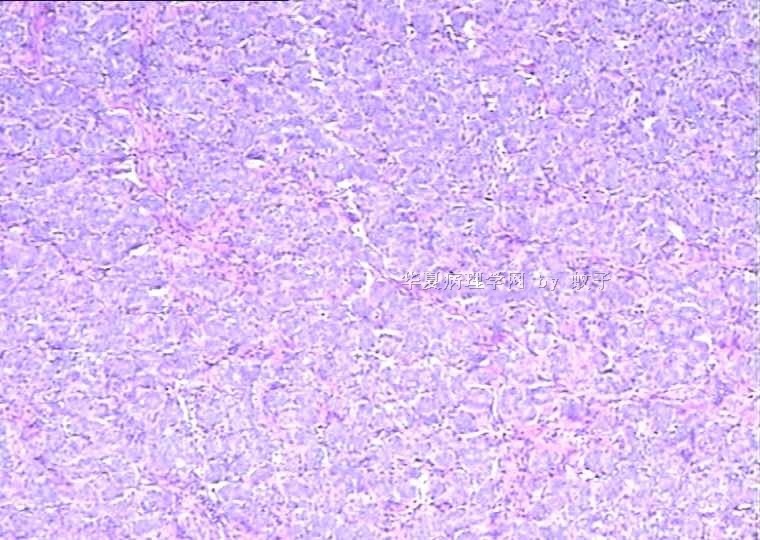

B2156乳腺活检

姓    名: ××× 性别:  女 年龄:  20

简要病史:  右乳包块8年。

肉眼检查:  灰白不整形组织一块,切面灰白,灰红,实性,质韧。

• 乳腺活检图2

图2

标签:乳腺腺病

旺识型腺病

腺病瘤(主要成份旺炽性腺病)部分区域为纤维腺瘤(管内型)

管状腺瘤